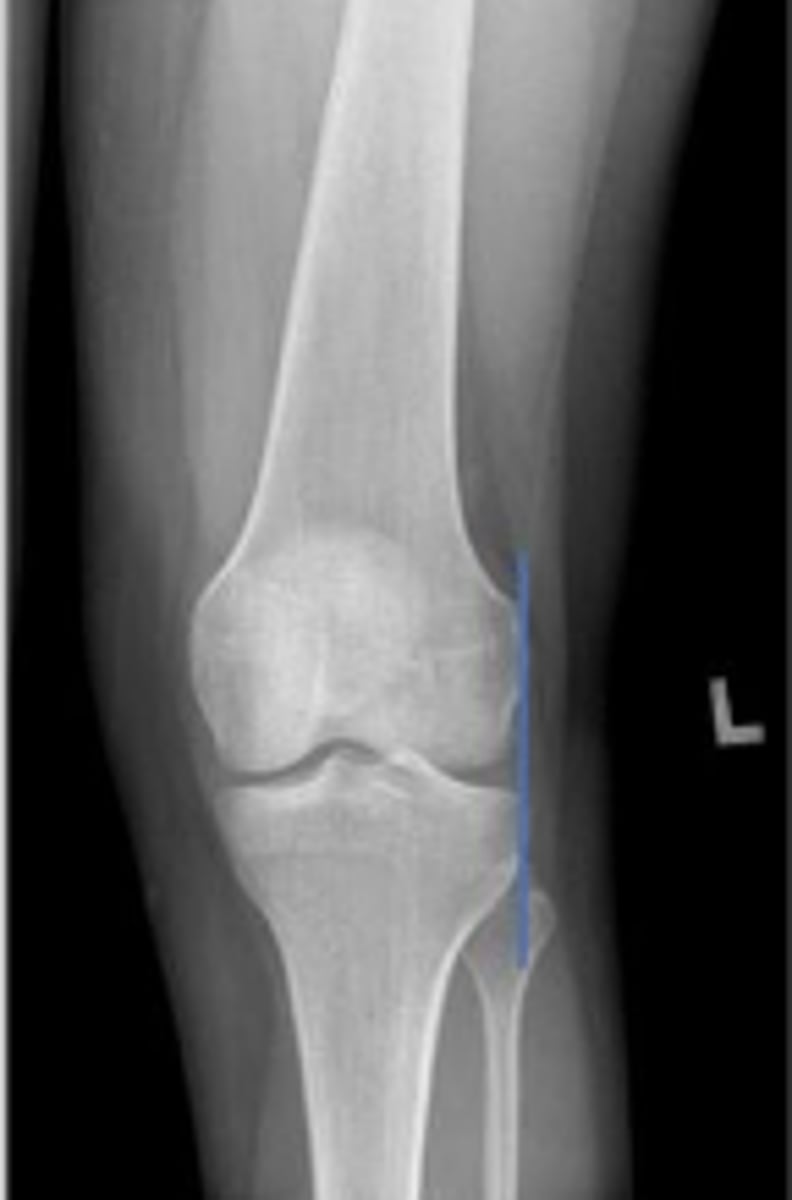

Right AP knee

What is the name of the radiographic view?